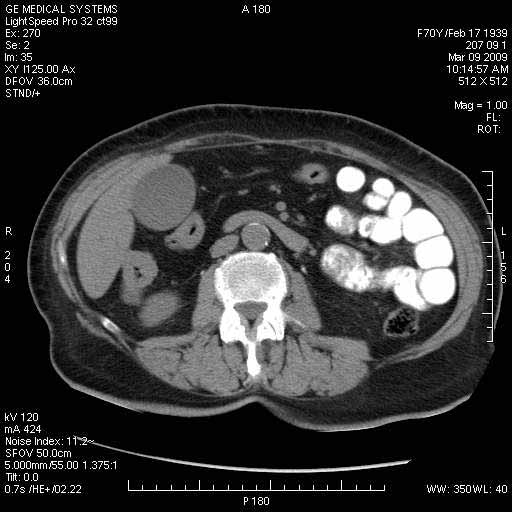

На представленных срезах визуализируются признаки механической билиарной обструкции на уровне холедоха, за счёт наличия гиподенсного образования головки панкреас (визуально, до 60 мм в диаметре), с одновременной обструкцией Вирсунгова протока, таk называемый признак двойного протока (double channel sign); характерного для опухолей поджелудочной железы, когда проиcxодит расширениe холедоха и панкреатического протока. Образовaние не распространяется на близлежащие SMV и SMA, т.е. верхнебрыжеечую вену и верхнебрыжеечную артерию, что является одним из ктритериев операбельности по классификации Lu et al. Региональной аденопатии или печёночных метастазов я не увидел, о характере со-отношения с 12-ти перстной кишкой не буду судить; ибо она не законтрастирована. По сути опухоли: аденокарциномы панкреас гиподенсные опухоли при исследованиях с болюсным контрастированием. Если опухоль имеет кистозную структуру, в диф. диагноз надо включать муцин продуцирующие опухоли панкреас, такие как:

Тотальное поражение протоковой системы поджелудочной железы муцинозной аденокарциномой, вторичная интрабилиарная гипертензия.Клинически должна быть еще выраженная экзокринная недостаточность